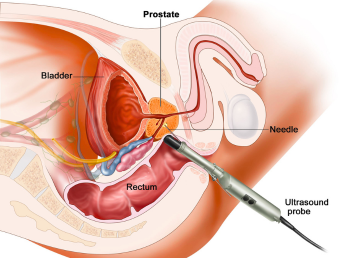

Prostate Disorders

1.endoscopic and minimally invasive urological surgeries.

Specialized procedures using advanced endoscopic techniques for precise treatment with minimal discomfort and faster recovery.